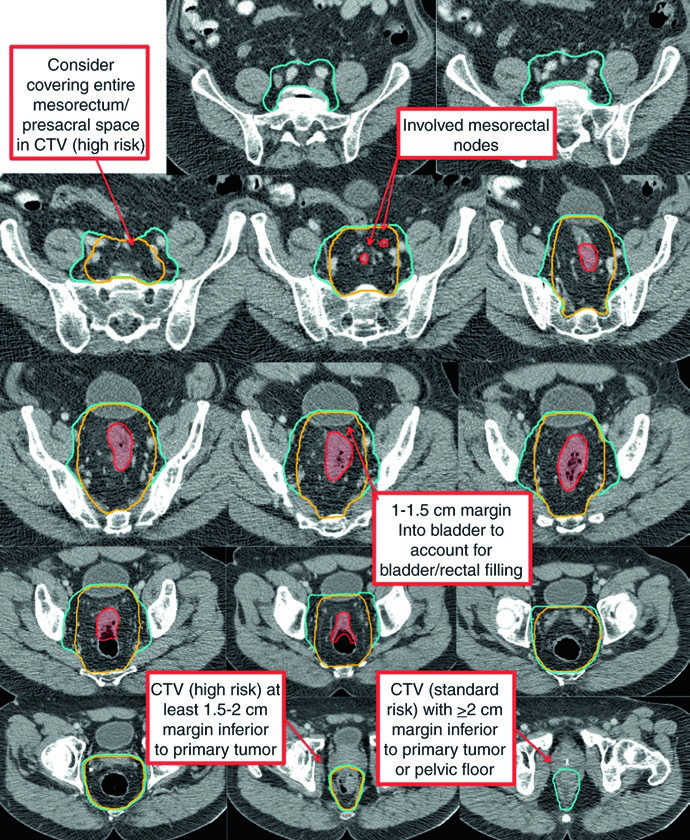

The high-risk CTV (CTV-HR) should include the GTV with a minimum 1.5 to 2 cm superior and inferior margin, plus the entire rectum, mesorectum, and presacral space. For grossly involved external iliac or inguinal nodes, the GTV-to-CTV margin should be at least 10 to 15 mm. In T4 tumors, a 1 to 2 cm margin into adjacent invaded organs (bladder, prostate, cervix) is added.

The standard-risk CTV (CTV-SR) covers the entire CTV-HR, mesorectum, and bilateral internal iliac lymph nodes. For T4 tumors with anterior organ involvement (bladder, cervix, prostate), the bilateral external iliac and obturator nodes must be included. If the primary tumor extends into the anal canal, bilateral external iliac and inguinal nodes are added to CTV-SR.

| CTV-HR | GTV-P and GTV-N with 1.5-2 cm margin superiorly and inferiorly, excluding uninvolved bone, muscle, and air. Minimum 10-15 mm margin for grossly involved external iliac or inguinal nodes. Entire rectum, mesorectum, and presacral space in the axial plane. 1-2 cm margin into adjacent organs for T4 tumors |

| CTV-SR | CTV-HR + entire mesorectum + bilateral internal iliac nodes. External iliac and obturator nodes for T4 with anterior organ involvement. Inguinal nodes for anal canal extension. Superior: L5/S1 or 2 cm above gross disease. Inferior: pelvic floor or 2 cm below gross disease. 0.7 cm margin around internal iliac vessels. 1-1.5 cm anterior margin into bladder |

T4 disease with anterior organ invasion significantly expands the treatment volume. The CTV-SR must cover the external iliac nodal region, and the anterior border of lateral fields needs adjustment to at least 1 cm anterior to the pubic symphysis.

| Mid-pelvis | Includes rectum, mesorectum, internal iliac region, and 1 cm margin into the bladder. Posterolateral to pelvic sidewall muscles or bone. Anterior: at least 1 cm into the posterior bladder. 7-8 mm margin around internal iliac vessels |

| Upper pelvis | Superior (perirectal): rectosigmoid junction or at least 2 cm cephalad to gross disease. Superior (nodal): bifurcation of common iliac vessels, approximately at the sacral promontory. 7-8 mm margin around internal iliac vessels, at least 1 cm anteriorly |